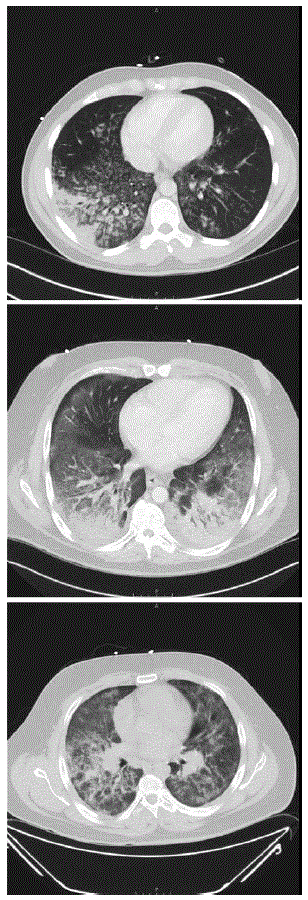

Изображения компьютерной томографии, показывающие диффузные инфильтраты в лёгких у трёх пациентов, 2019 год

Симптомы болезни EVALI включают затруднённое дыхание, кашель, боли в груди, жар и тошноту. В особо тяжёлых случаях заболевание может привести к дыхательной недостаточности, требующей госпитализации, а иногда и к летальному исходу. По данным Центров по контролю и профилактике заболеваний (CDC) в США, в 2019 году было 1479 сообщений о случаях EVALI, а число зарегистрированных смертей также выросло с 26 до 33 за тот же период. Эта цифра продолжает расти, и врачи бьют тревогу, что в будущем болезнь может стать настоящей эпидемией.